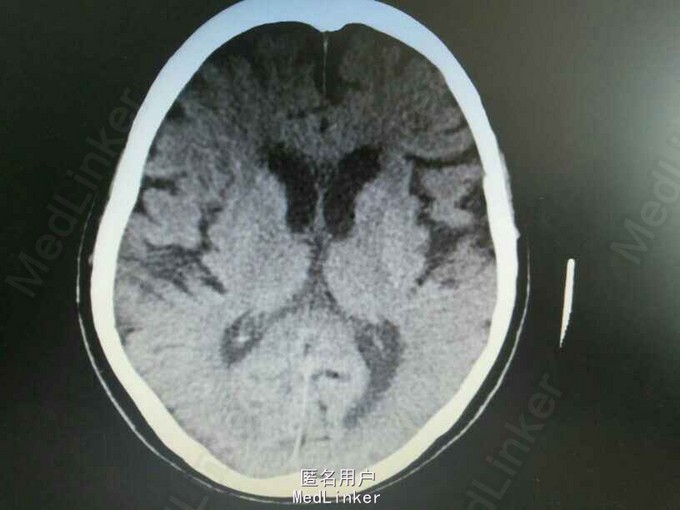

右侧颈内动脉开口重度狭窄

查体:神清,言语流利。高级皮层功正常。双侧眼球各方向活动充分,无复视、无眼震。双侧面纹对称,伸舌居中。四肢肌力5级。无肌肉萎缩。肌张力对称适中。双侧指鼻试验稳准,双侧跟膝颈试验稳准。双侧腱反射对称。双侧Hoffman'sign(-);双侧Babinski'sign、双侧Chaddock'sign(-)。 肾功能、离子、血糖、血脂、同型半胱氨酸、心肌酶、免疫八项、糖化血红蛋白、凝血功能、贫血三项、血尿便常规均正常。肝功能:总胆红素 17.6umol/L;输血前检查:TP-Ab阴性,HIV-Ab阴性,HbsAg阴性;抗心磷脂抗体IgG,IgM均阴性;心电图:窦性心律,66次/分,左心房扩大,非特异性房内传导阻滞,心脏呈逆钟向转位。胸片检查:右肺尖少许硬结灶,必要时追随观察。颈部血管超声:颈动脉弥漫硬化合并斑块,右侧颈内动脉起始段狭窄。左侧椎动脉阻力指数增加,左侧锁骨下动脉硬化斑块。左侧上肢动脉硬化。头颈CTA检查:头颈动脉硬化,管腔多发狭窄。右侧颈内动脉开口重度狭窄。经颅多普勒检查:左侧颈内动脉血流速度增快,双侧颈内动脉虹吸段血流速度增快,脑动脉硬化改变。

诊断:脑动脉供血不全;高血压3级 极高危 冠状动脉粥样硬化性心脏病 高脂血症。

右侧颈内动脉开口重度狭窄与头晕有关吗?需要介入治疗?